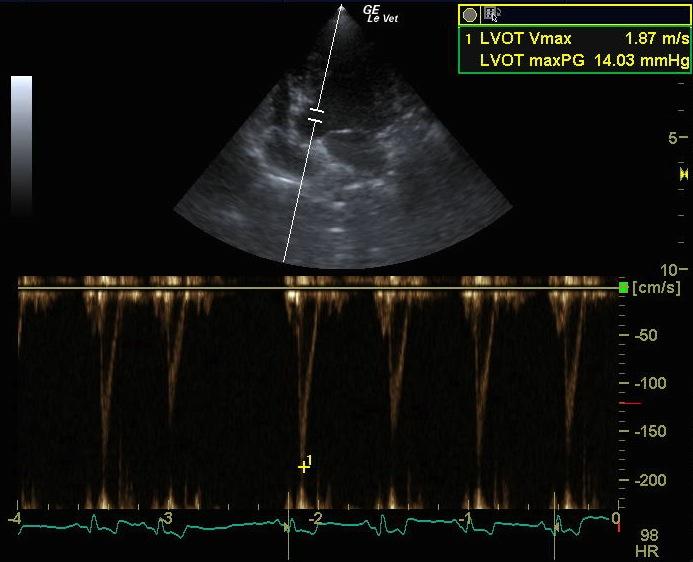

A 9-year-old FS mixed breed dog presented for evaluation of episodic coughing that appeared to be somewhat antibiotic responsive. Survey radiographs showed a normal cardiac silhouette, mild interstitial lung pattern, and an irregular shadow superimposing on the craniobasal cardiac silhouette and adherent to the left thoracic wall from the second to the forth rib. The radiographic changes had been present for almost 2 years.